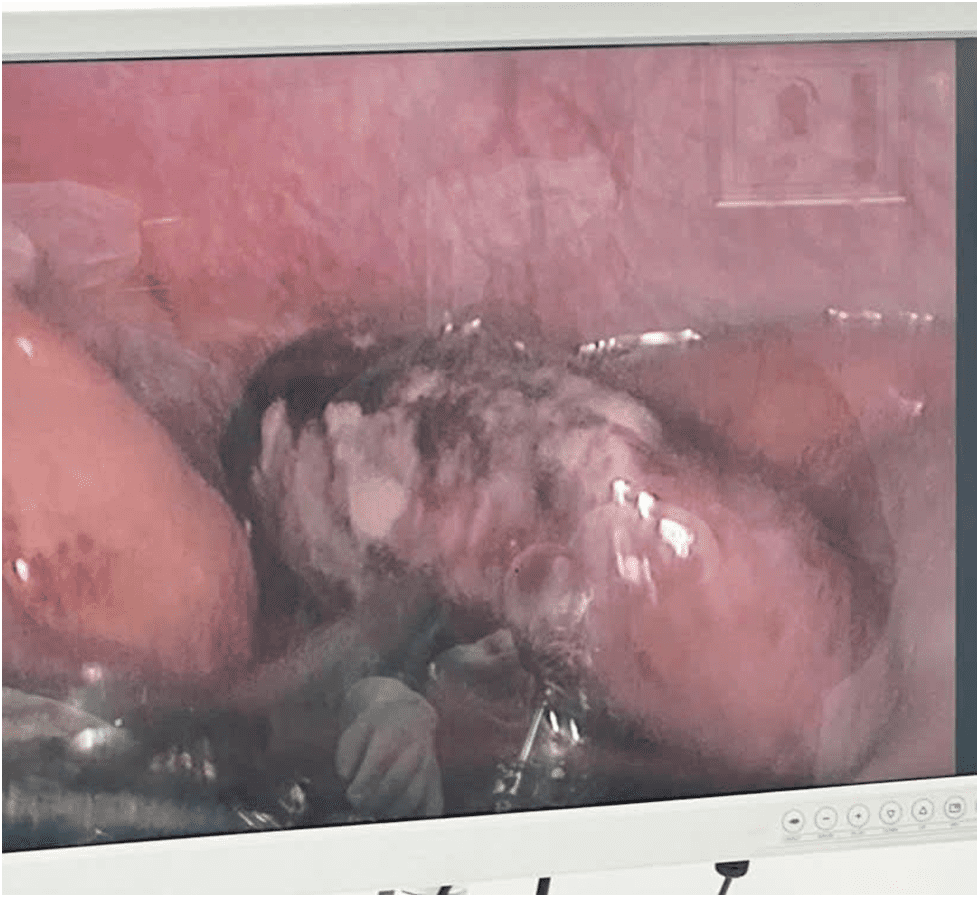

Một số hình ảnh bác sỹ trung tâm y tế Tân Uyên thực hiện mổ nội soi:

Phẫu thuật nội soi viêm ruột thừa là phương pháp điều trị tiên tiến, với ưu điểm nổi bật như: đường mổ nhỏ, ít đau sau mổ, hạn chế biến chứng và giúp người bệnh hồi phục nhanh hơn so với phương pháp mổ mở truyền thống. Nhờ đội ngũ bác sĩ có chuyên môn vững vàng, trang thiết bị được đầu tư đồng bộ, Trung tâm Y tế Tân Uyên đã xử lý thành công nhiều trường hợp viêm ruột thừa cấp, bao gồm cả các ca có diễn tiến phức tạp.